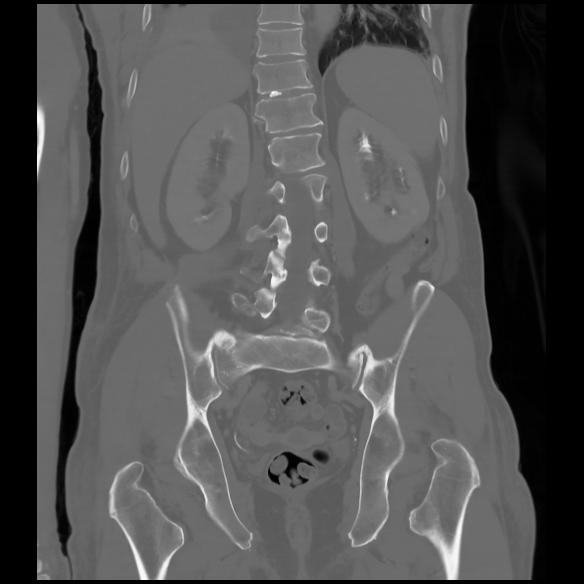

6 CUERPO,CE,Coronal,3.000,CUERPO,Coronal,